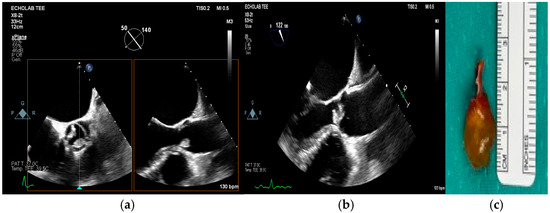

Multimodality Imaging in Infective Endocarditis: A Clinical Approach to Diagnosis

by Leonardo Brugiatelli, Francesca Patani, Carla Lofiego, Martina Benedetti, Irene Capodaglio, Pongetti Giulia, Francioni Matteo, Paolini Enrico, Nazziconi Marco, Kevin Maurizi, Furlani Giulia, Massari Arianna, Luciani Simone, Anselmi Benedetta, Gatti Chiara, Schicchi Nicolò, Fogante Marco, Tarsi Giovanni, Dello Russo Antonio, Di Eusanio Marco, Marini Marco and Fabio Vagnarelliadd Show full author list remove Hide full author list

Medicina 2025, 61(12), 2241; https://doi.org/10.3390/medicina61122241 - 18 Dec 2025

Infective endocarditis (IE) is a life-threatening condition with a rising incidence, demanding rapid and precise diagnosis. While echocardiography remains the cornerstone of initial evaluation, its limitations in complex cases—such as those involving prosthetic valves or cardiac devices—are well-known. This review synthesizes current evidence [...] Read more.

Infective endocarditis (IE) is a life-threatening condition with a rising incidence, demanding rapid and precise diagnosis. While echocardiography remains the cornerstone of initial evaluation, its limitations in complex cases—such as those involving prosthetic valves or cardiac devices—are well-known. This review synthesizes current evidence and guidelines to outline a practical, multimodality imaging approach for IE. We emphasize that integrating advanced techniques like cardiac computed tomography (CT) and [18F]-fluorodeoxyglucose positron emission tomography/computed tomography (FDG PET/CT) early in the diagnostic pathway, particularly in high-risk scenarios, significantly enhances diagnostic certainty, guides therapeutic decisions, and improves patient outcomes. A tailored imaging strategy, driven by clinical presentation and integrated within a multidisciplinary endocarditis team, is paramount for modern IE management. Full article

(This article belongs to the Special Issue Diagnosis and Treatment of Valvular Heart Diseases)

Show Figures

Figure 1